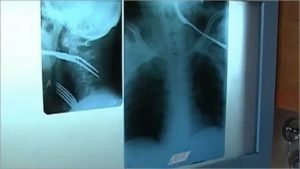

Врач знает, как вытащить рыбную кость из горла даже при тяжелом состоянии пациента, в медицинских учреждениях есть все необходимое оборудование для диагностики и лечения таких состояний. Обычно для диагностики достаточно простого осмотра горла – фарингоскопии.

В большинстве случаев бывает сложно определить место локализации кости. Если она застряла между ротоглоткой и гортаноглоткой, то возникают не локальные, а разлитые болевые ощущения. Чтобы обнаружить кость в пищеводе, необходимо провести эндоскопическое исследование.